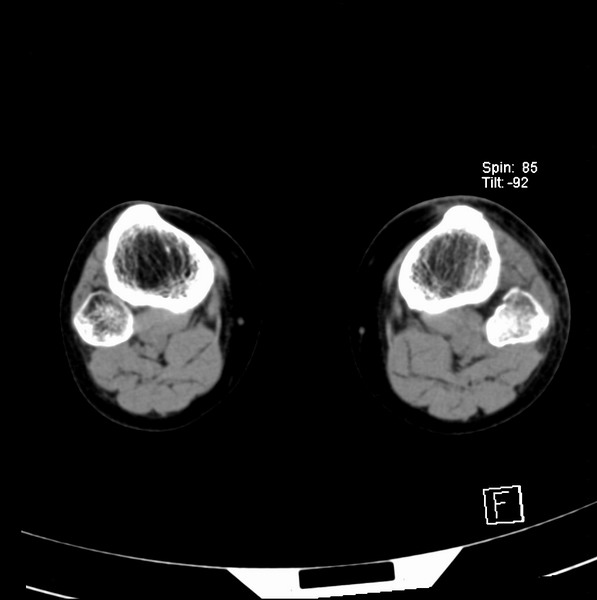

标题: CT21917:右腓骨小头是否骨软骨瘤? [打印本页]

标题: CT21917:右腓骨小头是否骨软骨瘤?

女、43.

不是骨软骨瘤,“牵拽征”,正常变异。有平片吗?

正常变异,“牵拽征”,比目鱼肌牵拽.

比目鱼肌附着点

支持 “牵拽征”——比目鱼肌牵拽。